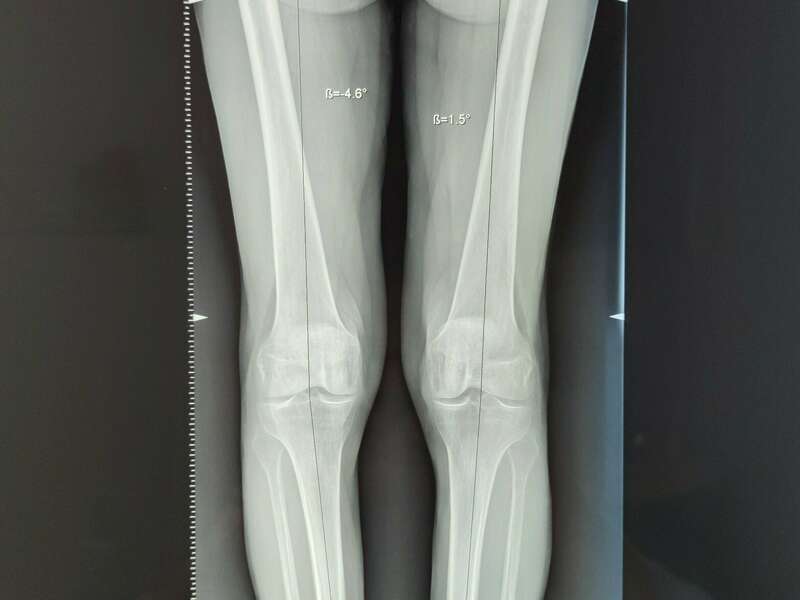

L’arthrose est un véritable problème de santé publique de nos jours. Elle représente l’une des principales causes de perte d’autonomie chez les personnes âgées. On estime qu’environ 65% des sujets de plus de 65 ans souffrirait d’arthrose. La gonarthrose concerne 30% des personnes de 65 à 75 ans. L’atteinte fémoro-tibiale interne est la plus fréquente et peut être due à une déviation de l’axe mécanique. L’atteinte fémoro-patellaire concerne plus souvent les sujets jeunes faisant suite à un traumatisme endommageant le cartilage ou à une instabilité de la rotule.

- Les déformations d’axe : genu varum (jambes arquées) et genu valgum (jambe en X)

Un alternative existe pour l’arthrose mono-compartimentale : l’ostéotomie tibiale plus ou moins fémorale du genou. Elle est indiquée chez des patients présentant une arthrose légère à modérée, avec une déformation d’axe mécanique (Genu Varum plus fréquent ou Genu Valgum) et trouve sa place chez des patients jeunes, sportifs, qui pratiquent des sports à impacts non recommandés chez les patients porteurs d’une prothèse unicompartimentale. Elle reste controversée dans l’arthrose mono-compartimentale sur genou normo-axé.